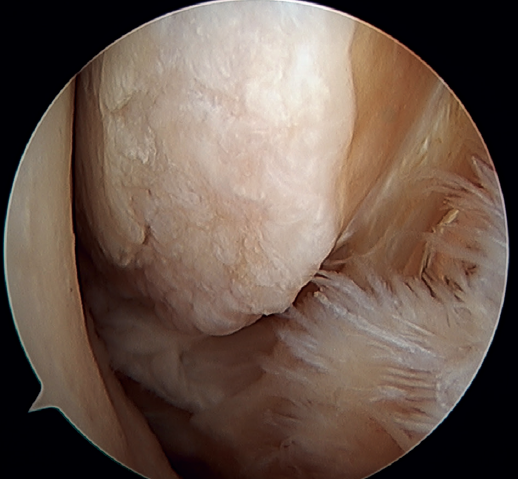

La principal indicación de esta reparación es la rotura del fascículo superior del LTFA de su inserción fibular, presentando una buena calidad tisular del remanente de ligamento (Figura 3).

Figura 3. A: identificación de la inserción fibular del LTFA (*) con excelente calidad del remanente tisular; B: técnica con dos implantes sin nudos y a través de un portal anterolateral único modificado; C: resultado final. P: peroné; T1: túnel talofibular; T2: túnel calcaneofibular.